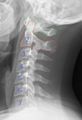

يصاب حوالي 15%(10-30%9 من أطفال متلازمة داون بعدم استقرار في المفصل المحور الفهقي. أسباب عدم الاستقرار غير معروفة ولكن يعتقد ان سببه هو ارتخاء في الرابط الذي يحفظ الوتد الخارج من الفقرة الثانية (المحور) قريب من الجزء الأمامي من الفقرة الأولى. أو لوجود عيب خلقي في تكوين الفقرتين العلويتين لأطفال متلازمة داون والسببين معا.

معظم الأطفال الذين لديهم عدم استقرار مفصل المحور الأطلسي لا يشتكون من شيء وليس له تأثير على صحتهم (تعرف هذه المجموعة بين الأطباء بالفئة التي بدو أعراض). وهناك مجموعة أخرى قد تصل إلى 1-2% من الأطفال المصابين بمتلازمة براون لديهم عدم استقرار في المفصل المحور الفهقي ويشتكون من آلام في الرقبة أو عدم القدرة على تحريك الرقبة بشكل تام أو ميل الرأس إلى أحد الجانبين أو لديهم صعوبة في المشي والحركة أو تغير في الاحساس الجلدي نتيجة لضغط وتد الفقرة الثانية على الحبل الشوكي (وتعرف هذه المجموعة بالفئة التي لديها اصابة للحبل الشوكي).